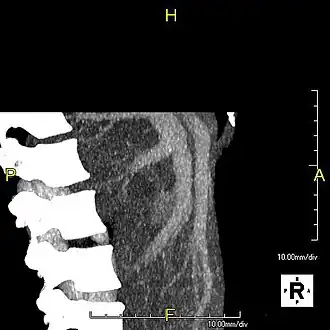

Maximum intensity projection (MIP) CT image as viewed anteriorly showing the anomalous hepatic veins coursing on the anterior surface of the liver -

Lateral MIP view in the same patient as previous image -